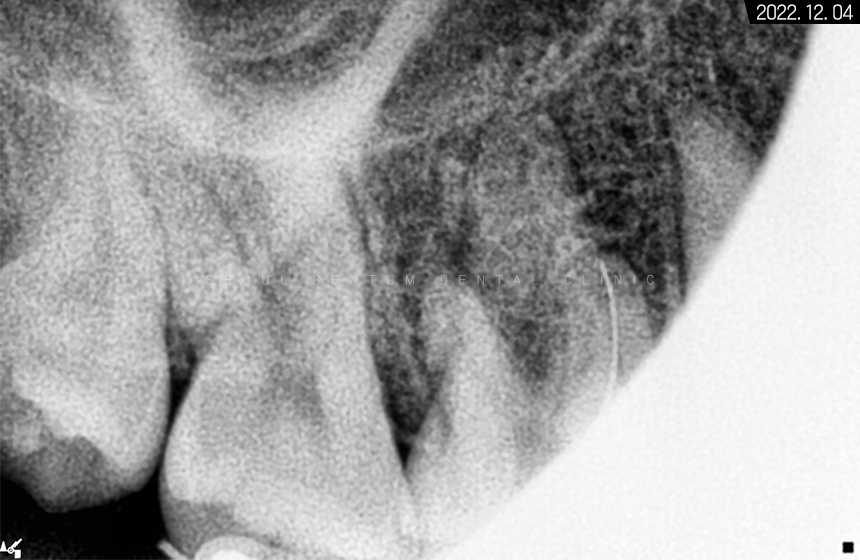

*기다란 막대기는 뿌리 끝 길이를

측정하기 위해 사용한 도구입니다.

교합면 우식을 제거하면서 근관 입구에 접근 후

근관장 길이 측정과 오염원 소파 및

소독 재료를 이용해서

근관을 멸균 상태로 만들고

그 후 안정 물질로 뿌리 끝까지

꼼꼼하게 메꿔드렸습니다.

그렇게 해서 3개의 뿌리가

흰색으로 잘 완성된 것을 볼 수 있습니다.

충전재로 잘 채워져 있고

레진으로 밀봉까지 마무리해두어서

하얗게 보이고 있는 것입니다.

다행히 뿌리가 막혀있지 않고

곧게 뻗어 있어서 간단하게 마칠 수 있었습니다.